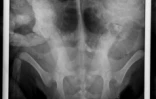

C'est suite à l'appel d'un groupe navigant au Cap Lahoussaye que Kélonia a récupéré un jeune mâle de tortue imbriquée samedi matin. Baptisée Lémira par des apnéistes quelques semaines plus tôt, la tortue a été ramenée au centre de soins de Kélonia alors qu'elle flottait en surface et ne plongeait pas à l'approche du bateau.Affaiblie et radiographiée, la tortue a été mise sous perfusion, mais malgré les soins prodigués, elle est morte dans l'après-midi. L'autopsie a confirmé le diagnostic de la radio, à savoir que la tortue est morte d'un blocage du transit intestinal qui devait durer depuis un moment vu son état de maigreur (18,4kg pour 65,5 cm de longueur de carapace). Le transit était bloqué par une grande quantité de cordes et fils de nylon, de quoi remplir une petite bassine.